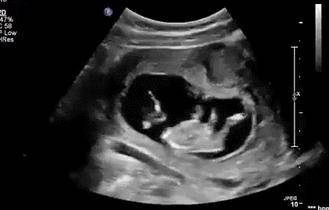

怀孕几个月开始胎动频繁?孕妈做好监测胎动的正确方法

宝宝胎动通常在28~30周之间相对比较频繁,宝宝胎动每一个人的具体情况不会完全一样,胎宝宝胎动的频繁程度,受腹腔的厚度等影响,只要孕妈自个感受到宝宝胎动是正常情况的就可以,不见得非要和其他人一模一样。

胎宝宝在宫腔内里的运动撞击到宫壁的小动作即为胎动,宝宝胎动受孕妈身体的敏感度、体型,宫内羊水数量,有没有怀过宝宝等影响,因此每位孕妈身体的感受都是不一样的。